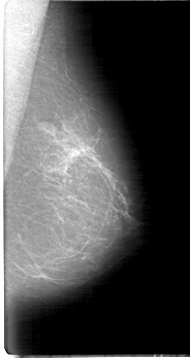

D_4070_1.LEFT_MLO

LEFT_CC LINES 5056 PIXELS_PER_LINE 2611 BITS_PER_PIXEL 12 RESOLUTION 43.5 NON_OVERLAY

LEFT_MLO LINES 5386 PIXELS_PER_LINE 2836 BITS_PER_PIXEL 12 RESOLUTION 43.5 NON_OVERLAY